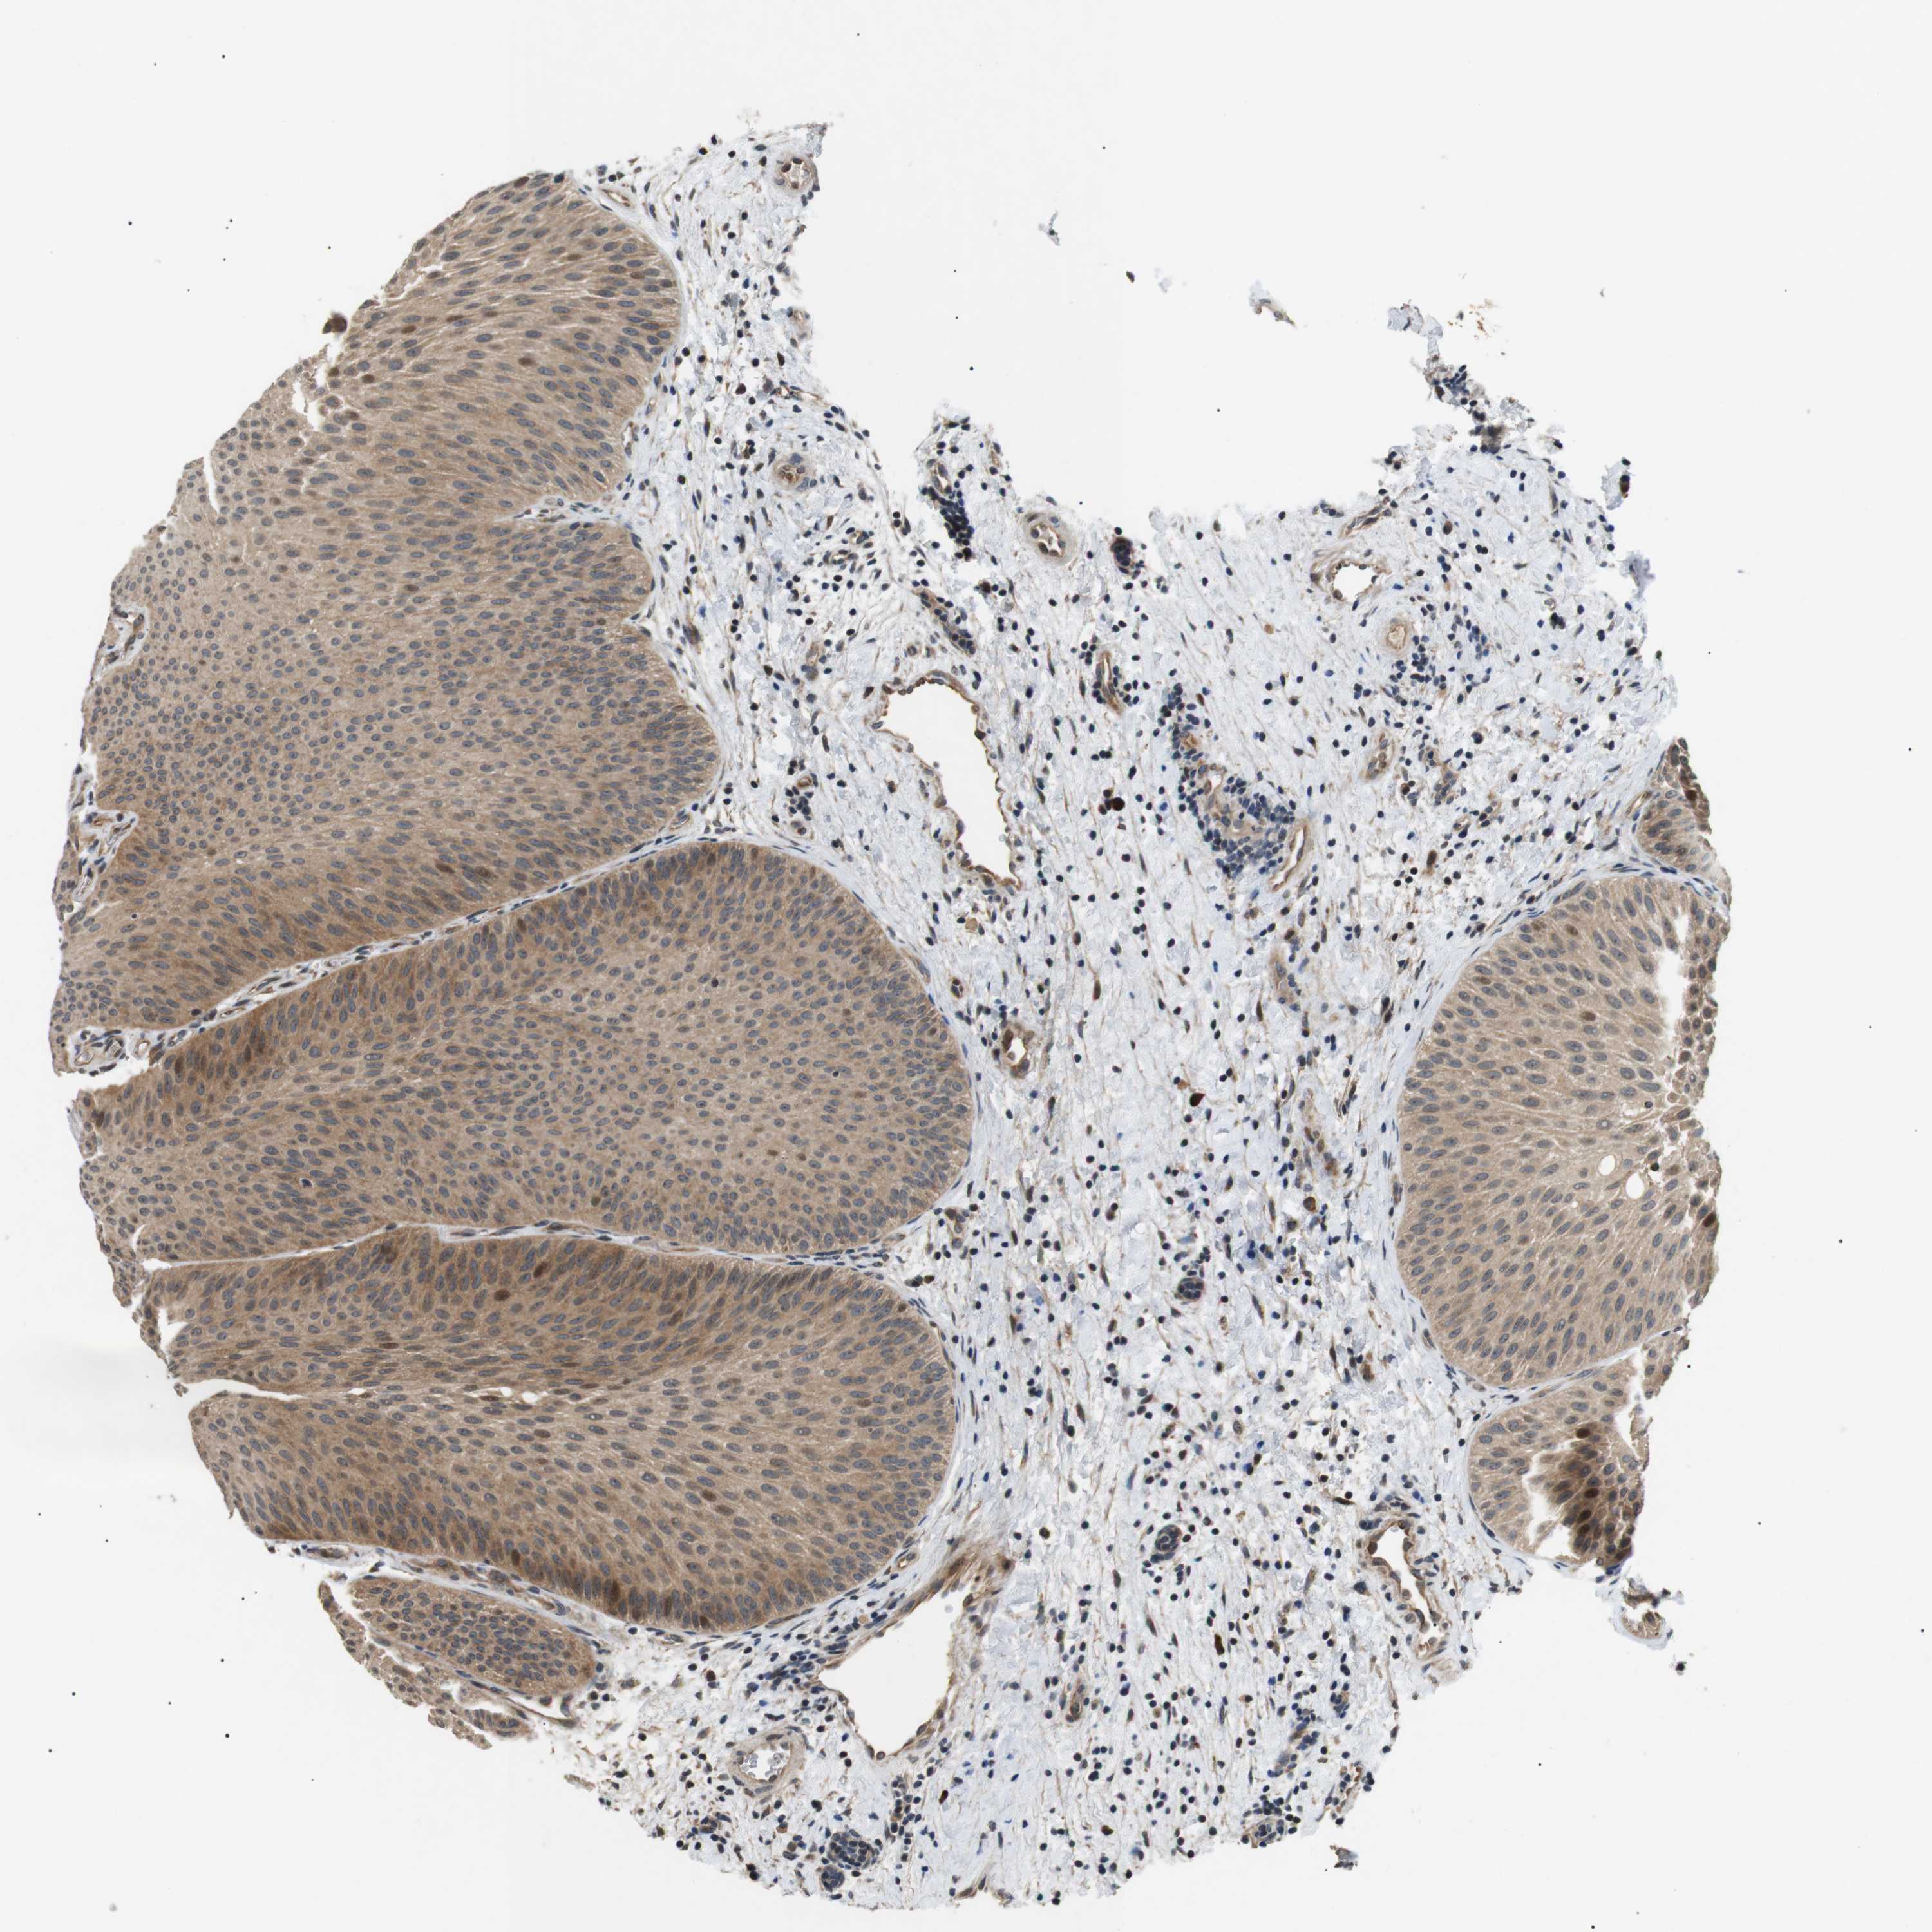

UROTHELIAL CANCER - Protein expressioni

A mouse-over function shows sample information and annotation data. Click on an image to view it in a full screen mode. Samples can be filtered based on level of antibody staining by selecting one or several of the following categories: high, medium, low and not detected. The assay and annotation is described here.

Note that samples used for immunohistochemistry by the Human Protein Atlas do not correspond to samples in the TCGA dataset.

Antibody stainingi

Antibody staining in the annotated cell types in the current human tissue is reported as not detected, low, medium, or high, based on conventional immunohistochemistry profiling in selected tissues. This score is based on the combination of the staining intensity and fraction of stained cells.

Each image is clickable and will lead to virtual microscopy that enables deeper exploration of all samples and also displays staining intensity scores, fraction scores and subcellular localization as well as patient and tissue information for each sample.

Antibody HPA014797

Staining

High

Medium

Low

Not detected

Intensity

Strong

Moderate

Weak

Negative

Quantity

>75%

75%-25%

<25%

None

Location

Nuclear

Cytoplasmic/membranous

Cytoplasmic/membranous,nuclear

Urothelial carcinoma, High grade

Urothelial carcinoma, Low grade